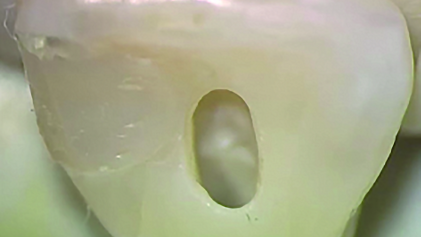

The cases shown in Figures 4 through 10—mostly done by IBAC members—make me very happy and afraid at the same time. What the heck are they doing? Little, tiny entries, leaving pulp chamber roofs intact, lateral pulp horns unroofed as well, or just total RCT through previously cut restorative cavities!

After getting over my initial shock at what they were accomplishing, I came to understand that the future of endo is very good in these extremely talented hands, and I saw that the procedure I was developing for endodontic surgery—CT-guided endodontic surgery (CT-GES)—could be applied to conventional treatment as well (Figs. 11a–12d).